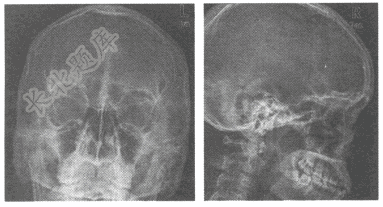

- 单项选择题患者,男,35岁,右眼外伤1天,眶面部肿胀.眼部疼痛,视物不清,X线片如下,最可能的诊断为

A、眶内壁骨折

B、上颌骨骨折

C、眶外侧壁骨折

D、正常眼眶

E、右眶内异物